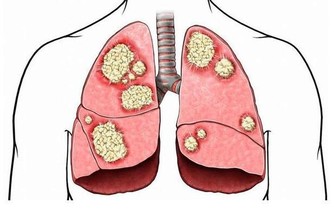

五、家裡最怕灰夏天悶熱、濕度大,使得灰塵更容易附著在空氣裡,進入人的皮膚和體內。由於肉眼很難發現,人們常常疏於清理,它們長期漂浮在空氣中,並大量附在物品表面,成為空氣中塵蟎及黴菌孢子的棲身地。這些臟東西會趁機進入呼吸系統,進而引發哮喘、鼻炎等多種疾病。

建議夏天應增加清潔的次數,兩三天打掃一次。